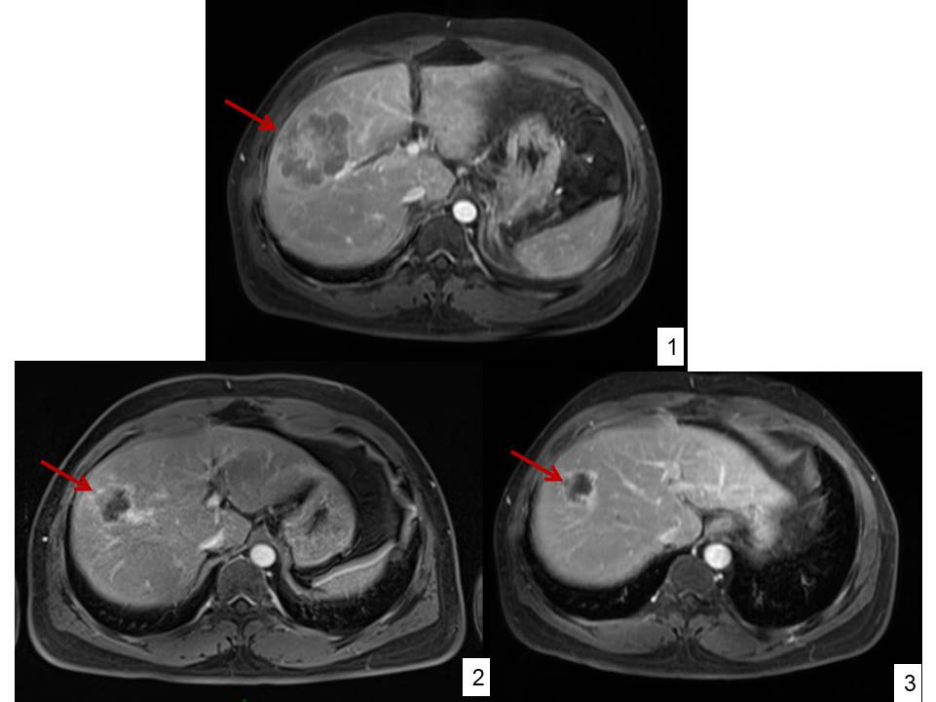

附图2:1)2021-12-16 治疗前:肝右前叶上段见大小约53mm×71mm团块状信号影。2)2022-2-25 2个疗程后:肝右叶占位大小约34mm×36mm,较前明显缩小。3)2022-4-12 4个疗程后:肝右叶占位大小约28mm×25mm,较前缩小。